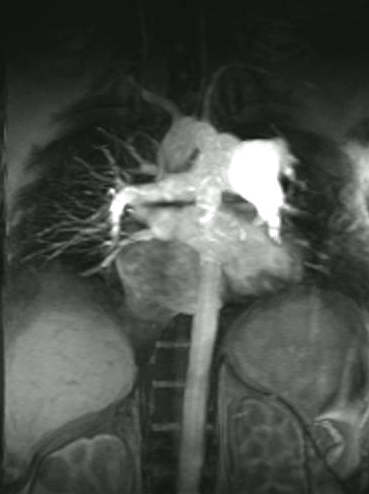

Scott WilliamsPulmonary ImagingGeneral > ChestCT > Images > HoneycombingApril 2, 2002Miscellaneous PulmonaryMisc > ARDSApril 2, 2002TumorTumor > Malignant > LungcancerApril 2, 2002MusculoskeletalPost-operative Bone Scanning:April 2, 2002Vascular AbnormalitiesVascular > HepatopulmApril 2, 2002PETPET > PET tumor imaging > CNSApril 2, 2002CardiacCardiac > Adultdz > CACalcApril 2, 2002MusculoskeletalMusculoskeletal > LymphApril 2, 2002CardiacCardiac > Valve > PS > Images > PS1April 2, 2002PETPET > PET tumor imaging > Thyroid CancerApril 2, 2002Previous PagePage 113 of 265Next PageTop StoriesCTNew benchmark helps monitor cumulative CT radiation doseThe findings highlight the need for systematic dose tracking and rigorous justification of imaging.Radiation Oncology/TherapyStudy questions routine use of radiotherapy after bone surgeryUltrasoundCEUS outshines color Doppler imaging for indeterminate kidney lesionsWomens ImagingWomen's Imaging MinnieCast, Episode 2: Risk-based vs. annual mammography screening, part 1Digital X-RayChest x-rays reveal atherosclerosis in patients undergoing amputations